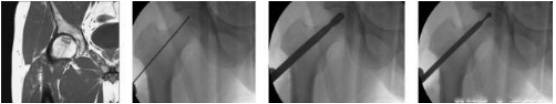

“糠萝卜”逐渐中空,长期负重进一步进展会出现“塌陷”,形似一个“被啃过的萝卜” 。 这个阶段尚无有效治疗股骨头坏死的办法,但治疗方式眼花缭乱,陷阱也多,因此到正规医院就诊是非常必要的 。 目前常用的有微创钻孔减压术缓解疼痛,有钻孔植骨术改善坏死病灶,旋转截骨保髋术等 。 还有一些被神话的方法如干细胞技术、血管介入治疗,其实只是花钱多效果差的尚未被认可噱头而已 。